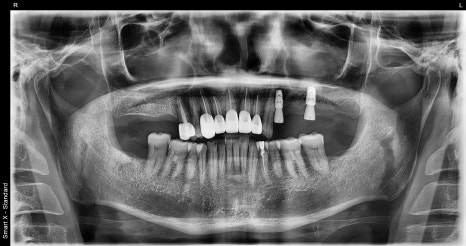

Full panoramic X-ray taken at the first visit

🖼️ Scene from the start of implant surgery

X-ray immediately after implant surgery and the intraoral view after surgery

During the detailed diagnosis, in addition to the front tooth trauma, advanced decay and bone loss were found in the right molar area.

Ultimately, that area required extraction, and implant surgery began together with bone grafting.

Before-and-after panoramic X-ray comparison (left: first visit / right: after treatment)